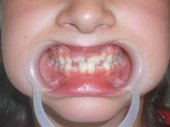

A la izquierda una mordida cruzada unilateral

tratada con efectividad con un tallado selectivo.

A la derecha un problema de masticación ineficaz por el lado izquierdo solucionado también con un tallado selectivo. |